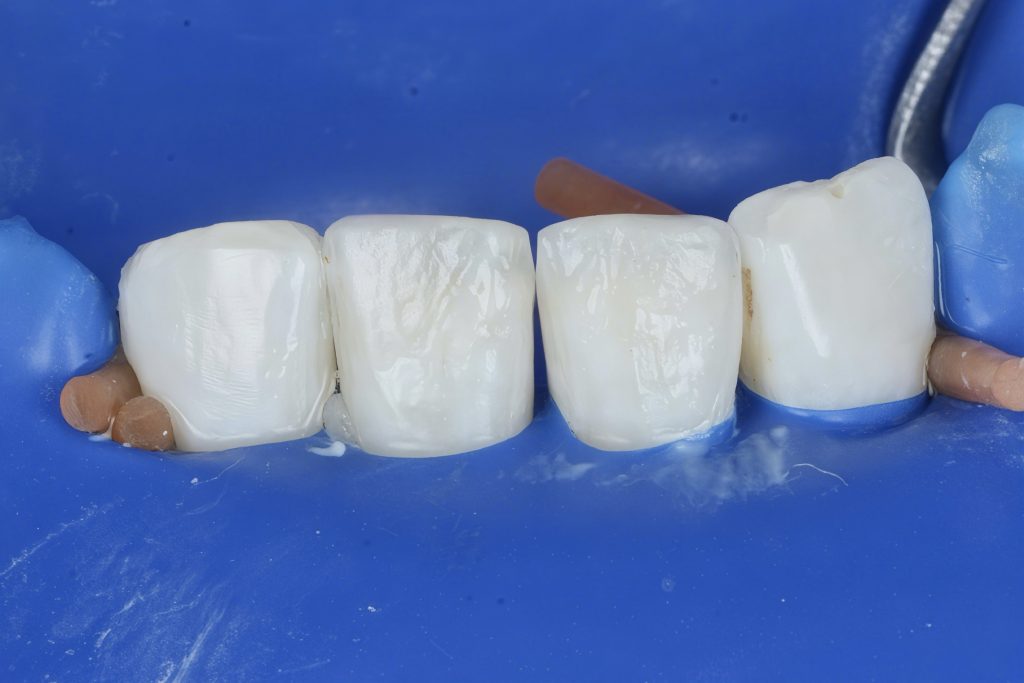

Composite veneers represent a conservative alternative to ceramics for anterior esthetic rehabilitation. With advances in resin composites, adhesive strategies, and isolation techniques, clinicians can achieve highly esthetic and functional results with minimally invasive protocols. This case presents the restoration of anterior teeth with direct composite veneers under strict isolation, following a biomimetic layering approach.

The patient presented with anterior teeth showing cervical wear, incisal edge defects, and discoloration. The esthetic concern was compounded by loss of natural morphology and translucency. The treatment plan focused on direct composite veneers to restore harmony, form, and function in a minimally invasive manner.

1. Isolation and Preparation

•Rubber dam isolation was secured using floss ligatures and teflon retraction to ensure clean margins and soft tissue displacement.

•Only superficial enamel cleaning and beveling of margins were performed, maintaining maximum enamel for adhesion.

2. Matrix and Shape Control

•Transparent silicone index and Mylar strips were used to guide palatal contour and proximal form.

3. Adhesive Protocol

•Selective enamel etching (37% phosphoric acid) was performed for 30 seconds.

•A universal adhesive system was applied, air-thinned, and light-cured to establish a strong hybrid layer.

4. Composite Layering Technique

A biomimetic incremental layering strategy was used:

•Palatal Shell: Created with a translucent enamel shade by SAREMCO composite using the silicone index.

•Dentin Core Build-up: Body shade composite with 3m easy match layered to reproduce dentin opacity and saturation.

•Incisal Halo & Effects: Opaque tint and high-value composite by SDI and Tokyuma were used in the incisal edge for a natural halo effect.

•Final Enamel Layer: A microfilled enamel by 3m easy match shade natural composite was applied to reproduce surface gloss and translucency.